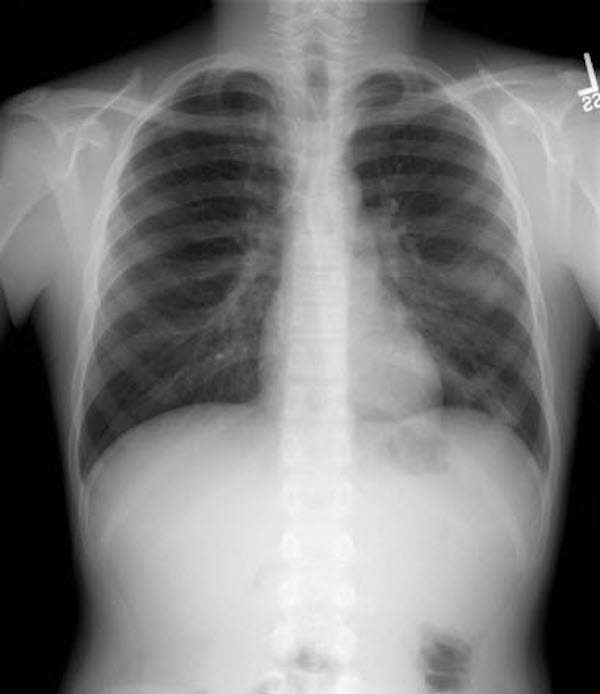

▼22歲的黃姓女大生修習音樂系,過去吹奏喇叭也曾出現輕微咳嗽症狀,她則會休息幾天再吹。這次卻反覆發燒、咳嗽,4月份就醫時,才由X光照出胸腔有大面積的肺炎。(示意圖)